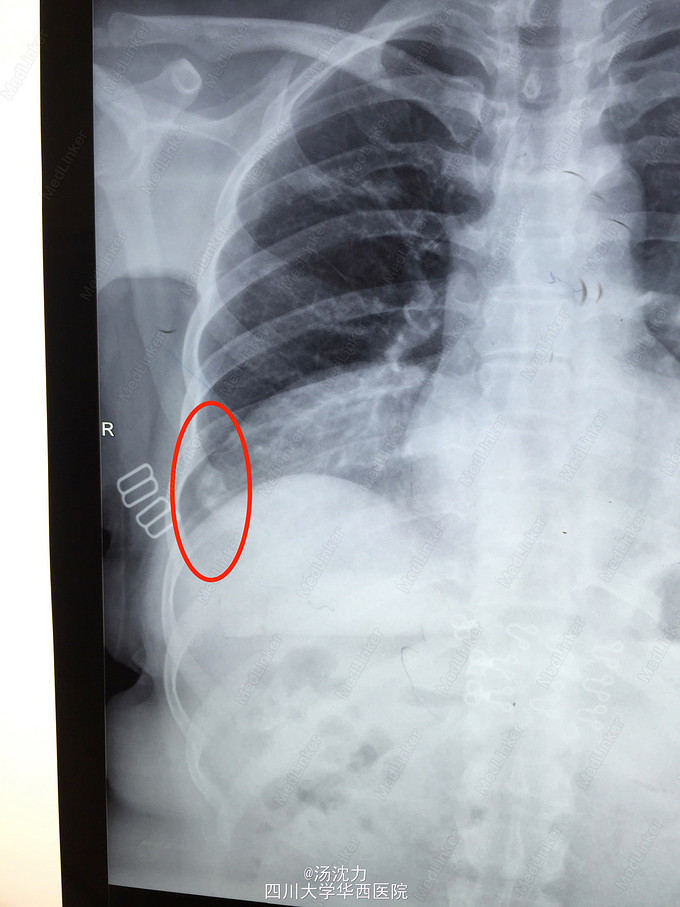

肋骨转移还是陈旧性骨折?

患者乳腺癌术后规律复查,未诉骨折病史及明显不适。最近三年胸片如图。2年前曾行骨扫描,怀疑该处为陈旧性骨折。

2年前和1年前的病变比较起来比较像骨折修复的感觉,但是今年的胸片变化看着又像是明显的溶骨改变,加上患者未诉明显的外伤史,所以更倾向于怀疑是转移瘤。